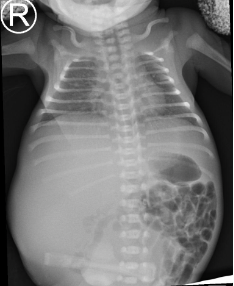

Preterm premature rupture of membranes (pPROM) before 22–24 weeks of gestation is considered previable and poses a high risk to the chances of successful delivery. Multicystic dysplastic kidney (MCDK) is the most common form of dysplasia of this organ, usually affecting 1 kidney. A prenatal suspicion of MCDK requires escalation of the clinical process to a reference center qualified and equipped for further diagnosis and treatment. We present a unique case of prenatal pPROM at 19 weeks of gestation in a pregnancy complicated by fetal MCDK as an interesting obstetric and neonatal patient story. We have not found any published evidence on the impact of coexisting fetal congenital malformations on a pregnancy affected by previable pPROM.

Balasundaram M, Chock VY, Wu HY, Blumenfeld YJ, Hintz SR. Predictors of poor neonatal outcomes in prenatally diagnosed multicystic dysplastic kidney disease. J Perinatol 2018;38(6):658-64.

Pettit S, Chalmers D. Neonatal multicystic dysplastic kidney with mass effect: A systematic review. J Pediatr Urol 2021;17(6):763-8.